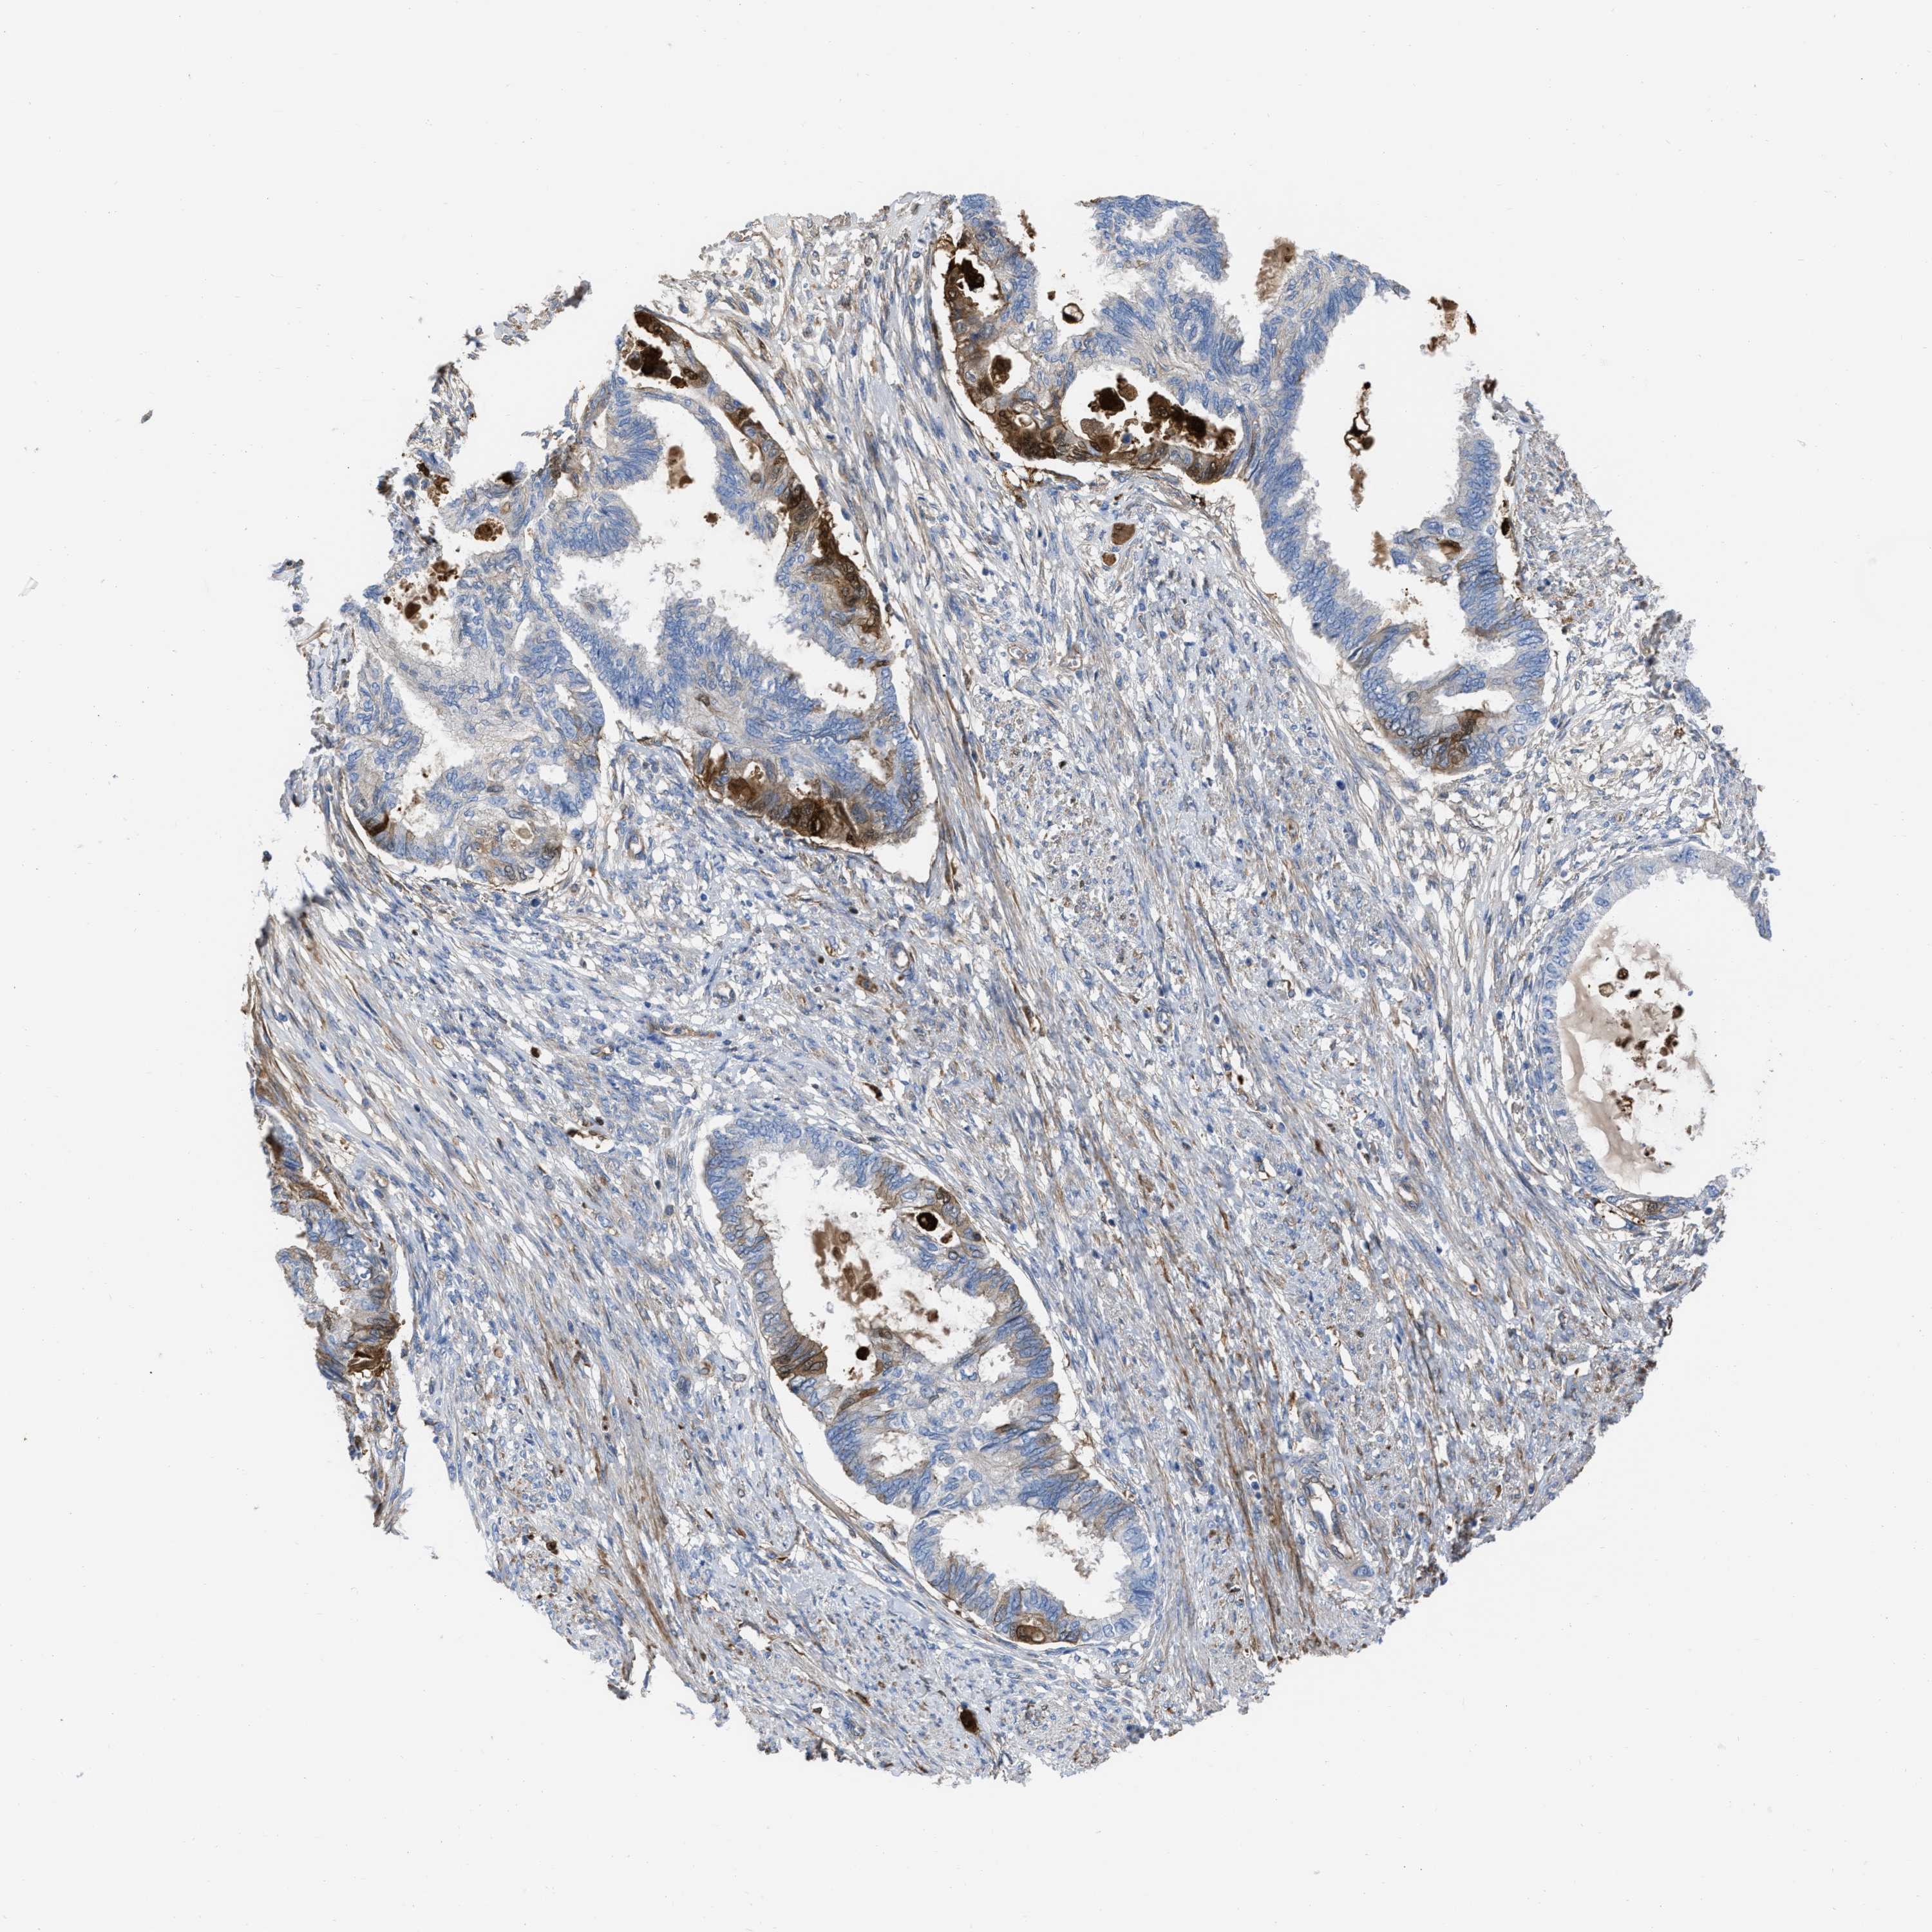

CERVICAL CANCER - Protein expressioni

A mouse-over function shows sample information and annotation data. Click on an image to view it in a full screen mode. Samples can be filtered based on level of antibody staining by selecting one or several of the following categories: high, medium, low and not detected. The assay and annotation is described here.

Note that samples used for immunohistochemistry by the Human Protein Atlas do not correspond to samples in the TCGA dataset.

Antibody stainingi

Antibody staining in the annotated cell types in the current human tissue is reported as not detected, low, medium, or high, based on conventional immunohistochemistry profiling in selected tissues. This score is based on the combination of the staining intensity and fraction of stained cells.

Each image is clickable and will lead to virtual microscopy that enables deeper exploration of all samples and also displays staining intensity scores, fraction scores and subcellular localization as well as patient and tissue information for each sample.

Antibody HPA019769

Staining

High

Adenocarcinoma, NOS